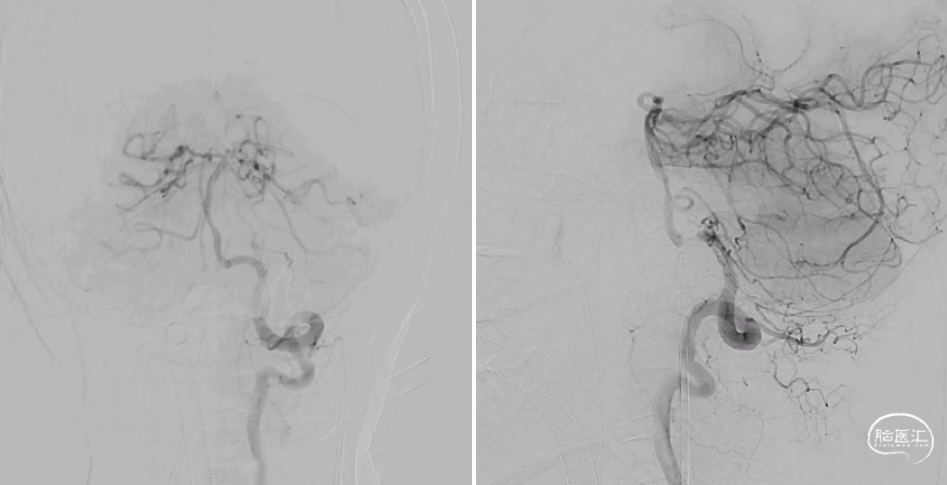

患者术后半年于当地医院复查血管造影,提示瘘口完全栓塞,未见复发(图8)。

图8. 术后半年复查脑血管造影。